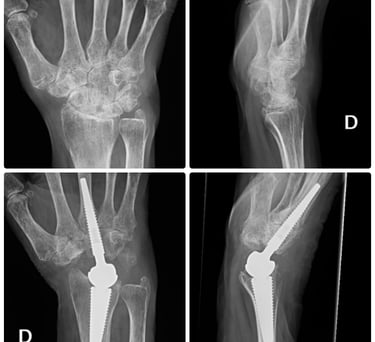

Prótesis de muñeca y dedos.

Prótesis para rizartrosis.

Osteotomías correctoras con planificación 3D

Transferencias nerviosas y tendinosas

Artrodesis totales o parciales

Especialistas en cirugía prótesica

Tratamiento de secuelas y casos complejos

Prótesis de tobillo y artrodesis avanzada

Soluciones definitivas para artrosis avanzada

✔ Artrosis tibioastragalina

✔ Artrosis subastragalina

✔ Hallux rigidus severo

➡ Prótesis total de tobillo

➡ Artrodesis anatómica

➡ Recuperación funcional orientada al paciente activo